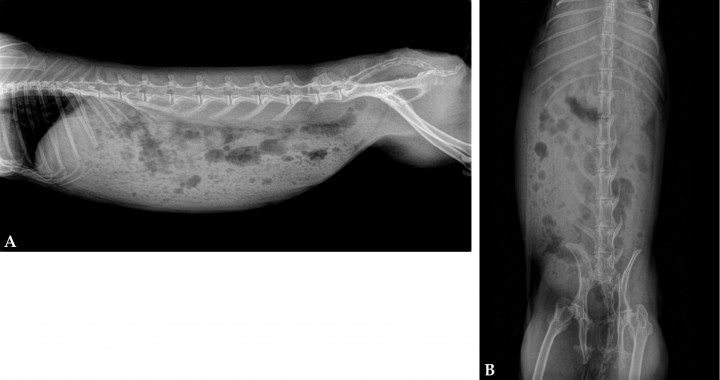

En las radiografías realizadas de la cavidad abdominal (Fig. 1) se apreciaba distensión estomacal con contenido gástrico y gas a nivel intestinal compatible con hipomotilidad gastrointestinal.

<p>Radiografías abdominales. (<strong>A</strong>) Proyección lateral derecha. (<strong>B</strong>) Proyección ventrodorsal. Se aprecia distensión gástrica con contenido estomacal, aumento de gas en intestino, ausencia de contenido en su porción más caudal.</p>

Radiografías abdominales. (A) Proyección lateral derecha. (B) Proyección ventrodorsal. Se aprecia distensión gástrica con contenido estomacal, aumento de gas en intestino, ausencia de contenido en su porción más caudal.

Las radiografías abdominales realizadas en conejos con TLH muestran anormalidades poco específicas, siendo las alteraciones más constantes la hepatomegalia y la morfología redondeada de los márgenes hepáticos.[ Graham JE, Orcutt JC, Casale SA, et al. Liver lobe torsion in rabbits: 16 Cases (2007 to 2012). J Exot Pet Med 2014; 23:258-265. , Wenger S, Barrett EL, Pearson GR, et al. Liver lobe torsion in three adult rabbits. J Small Anim Pract 2009; 50:301-305. [PubMed] , Pignon C, Donnelly TM, Mayer J. Hepatic lobe torsion in a rabbit (Oryctolagus cuniculus). Prat Méd Chirur l’Anim Comp 2013; 48(3): 91-98. ] La presencia de distensión gástrica y gas en estómago e intestino son sugestivos de hipomotilidad gastrointestinal u obstrucción.